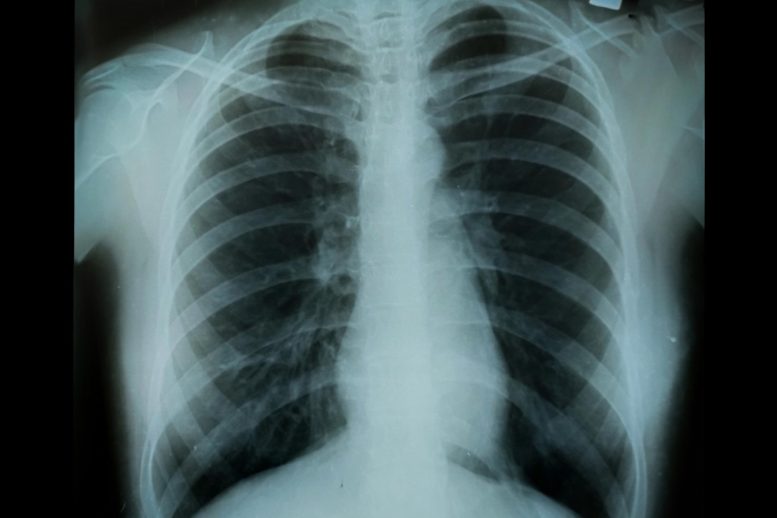

Regardless of affecting over 30 million Individuals, COPD stays dangerously underdiagnosed. As a number one explanation for loss of life, this continual respiratory illness continues to assert lives, but consciousness and early prognosis efforts lag behind. With loss of life charges rising and girls disproportionately affected, specialists stress the pressing want for schooling and prevention. Persistent Respiratory Ailments: A Main Trigger […]